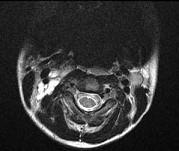

问题 女,13岁,皮肤有多发结节和多发棕色素斑,MR表现如图,最可能的诊断是()

选项 A.脸颜面血管瘤病 B.结节性硬化 C.神经纤维瘤病 D.听神经瘤 E.松果体瘤

答案 C